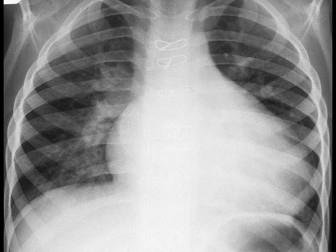

问题 女孩11岁,胸骨左缘第2肋间听到Ⅱ级收缩期杂音,肺动脉瓣区第二心音固定分裂。胸片示如图,右房右室增大。心电图为不完全右束支阻滞,最可能的诊断是 ( )

选项 A、法洛四联症 B、动脉导管未闭 C、室间隔缺损 D、肺动脉狭窄 E、房间隔缺损

答案 E